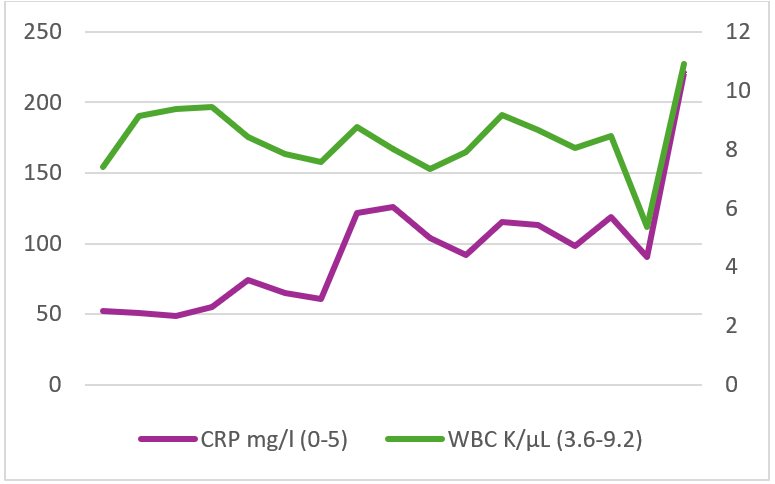

Trends of inflammatory markers during hospitalization are displayed in Figure 1.

Figure 1: Time course of white blood cell count and serum C-reactive protein level during patient hospitalization. WBC, White blood cell; CRP, C-reactive protein.